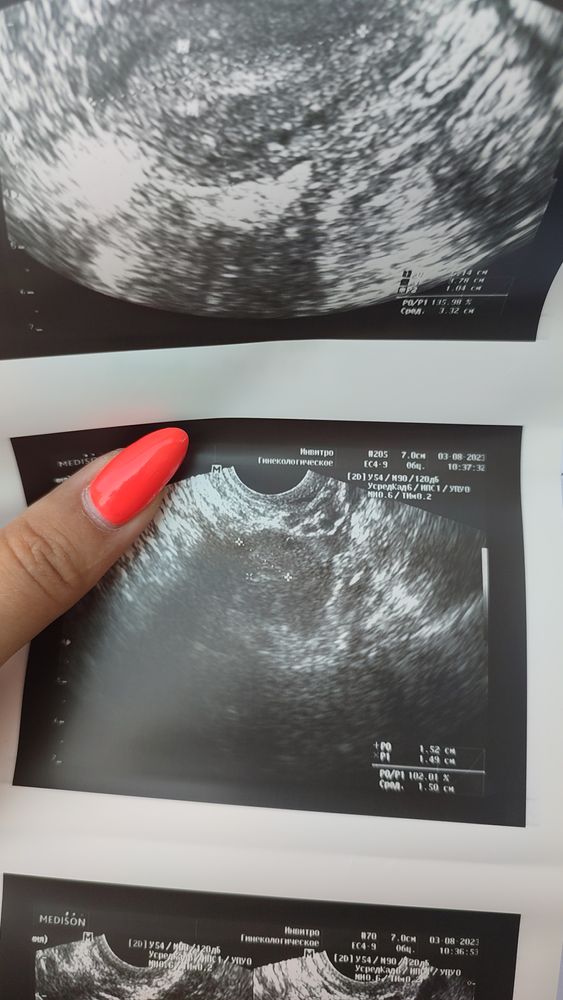

УЗИ ничего не понятно,но очень интересно

Евгения П, мне сказали на ВБ не похоже гинеколог сказала что жди месячные будут через неделю но хгч на всякий случай пересдай

Кулакова Александра, это выброс денег лишний , после месячных надо будет в овулю пойти и фолликулометрию сделать , что то не понятно , что там с ними . Нужно заниматься этим вопросом.